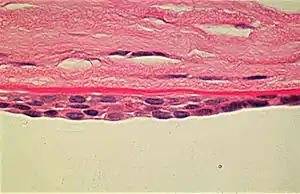

| Appearance of the abnormal corneal endothelial cells that have become transformed into stratified squamous epithelium. Periodic acid Schiff (PAS) stain | |

Vacuoles are demonstrated in the posterior parts of the cornea. The vesicles are located on the endothelial surface. The corneal endothelium is normally a single layer of cells that lose their mitotic potential after development is complete. In posterior polymorphous corneal dystrophy, the endothelium is often multilayered and has several other characteristics of an epithelium, including the presence of desmosomes, tonofilaments, and microvilli. These abnormal cells retain their ability to divide and extend onto the trabecular meshwork to cause glaucoma in up to 40% of cases.[2]